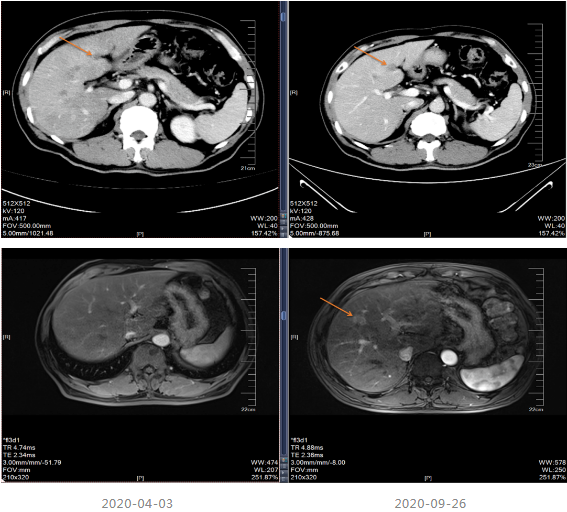

2019-03-14行上腹部增强CT,显示肝内散在的多发圆形稍低密度灶,大小不等,边界欠清晰,较大者直径约5.2cm,其内密度不均,增强扫描病灶周边有强化,内部有更低密度区液化坏死区,考虑转移瘤;胆囊多发结石;双肾多发结石,直径小于0.2cm;扫描范围内结肠肝区管壁增厚,管腔狭窄,增强扫描可见明显强化。

△2019-03-14上腹部(包括肝、胆、脾、胰范围内)平扫+增强

治疗期间于2019-07-13及2019-12-19进行疗效评估,疗效评价PR,建议患者切除原发灶,患者拒绝。CEA、CA199降至正常范围。

局部治疗:2020-09-26复查MRI提示部分病灶较前缩小,部分增大,于2020-10-22至武汉同济医院行“肝脏病灶微波消融术”,后继续口服卡培他滨至2021-5。